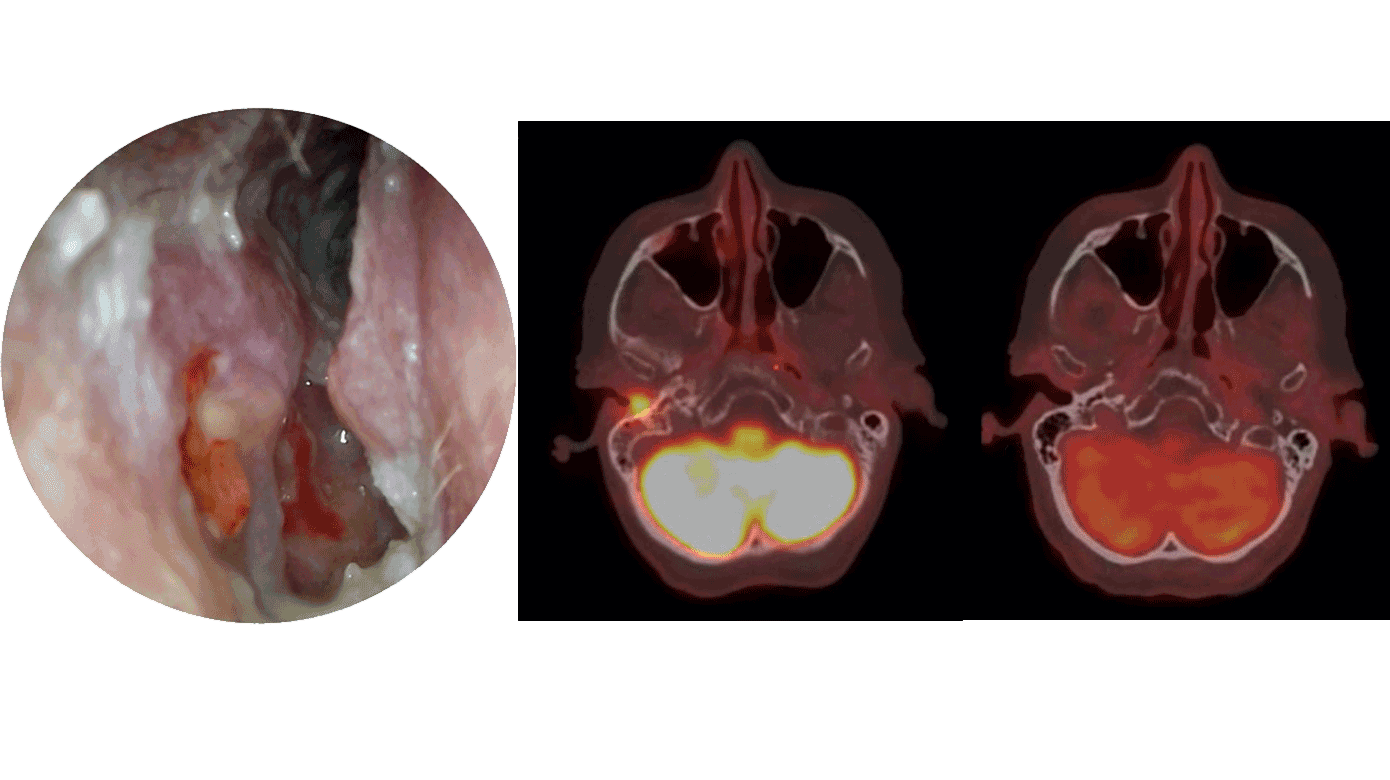

En 68-årig kvinde, kendt med insulinkrævende diabetes mellitus og myelomatose med komplet remission, debuterede med intermitterende øresmerter på højre øre samt fornemmelse af nedsat hørelse og rungen på øret. Otomikroskopi viste granulerende væv og knogleblotning i øregangsgulvet og bagvæggen (Figur 1A). Trommehinden sås reaktionsløs, og mellemøret var luftfyldt. Audiometri viste et lille, konduktivt høretab på højre side. På mistanke om kolesteatom blev der taget biopsier fra det granulerende væv, og patienten blev henvist til subakut MR-skanning, som viste udbredt væskeansamling i pars petrosa, os temporale og mastoidceller højresidigt, men uden sikre tegn på kolesteatom. I biopsierne fandtes erosiv inflammation og granulationsvæv uden tegn på hverken kolesteatom eller malignitet. Der blev foretaget PET-CT, som viste bløddelsudfyldning i højre, ydre øregang med fluordeoxyglukose (FDG)-aktivitet (Figur 1B).

Ved nærmere gennemgang af patientens medicinliste faldt mistanken på i.v. indgift af bisfosfonatpræparatet pamidronat, som patienten havde fået for sin myelomatose gennem to år. En sjælden bivirkning til dette præparat er osteonekrose i øregangen. Pamidronat blev seponeret, og der blev foretaget jævnlig, lokal débridement, hvorved knogleblotningen gradvist helede op.